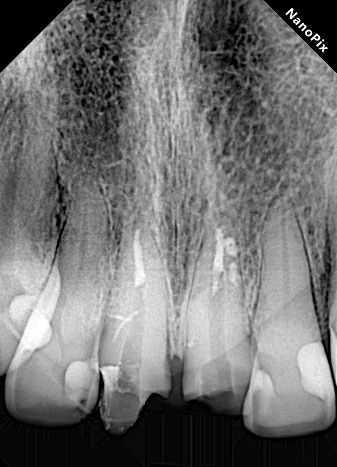

Raio X portátil e sistema de captura de imagem

Os aparelhos de raio X portáteis possibilitam ergonomia e praticidade na execução de radiografias intrabucais. Associadas ao sensor digital possibilitam menor tempo de exposição ao paciente e profissional.